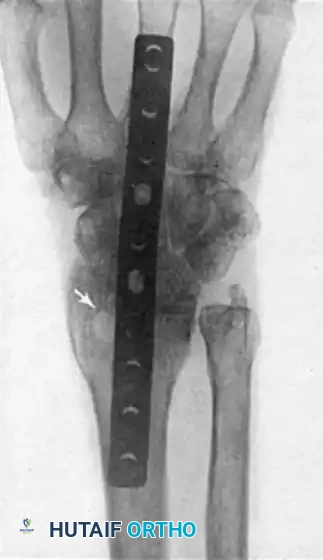

The technique popularized by Weiss and Hastings utilizes a rigid dorsal plate spanning the radius, carpus, and third metacarpal. This method provides superior biomechanical stability, high fusion rates, and eliminates the need for prolonged postoperative cast immobilization.

4. Plate Selection and Application

• Implant Selection: Select a pre-contoured 3.5-mm dynamic compression plate (DCP) designed specifically for wrist arthrodesis. The plate must be of sufficient length to ensure that at least six bone cortices (three screws) are engaged in the distal metacarpal, and six bone cortices are engaged in the distal radius.

Image

• Fixation Sequence: The order of screw placement is critical for achieving compression and maintaining alignment.

1. Distal Fixation: After positioning the plate, secure the distal screws to the third metacarpal first. This establishes the distal anchor.

2. Graft Placement: Before securing the proximal screws, pack the harvested cancellous bone graft from the distal radius tightly into the denuded radiocarpal and midcarpal joint spaces.

3. Proximal Fixation: Fix the plate to the distal radius. Utilizing the dynamic compression holes will help compress the carpus against the radius.

4. Carpal Fixation: Place one or two cancellous lag screws through the midportion of the plate directly into selected carpal bones, most critically the capitate. This neutralizes the fusion mass and prevents intercalated segment toggle.